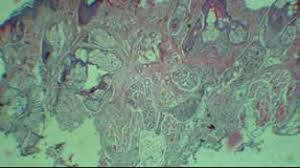

سندرم پری-رومبرگ با تحلیل پیشرونده (یا از بین رفتن) بافت زیر جلدی در نیمی از صورت مشخص می شود که معمولاً از دوران کودکی آغاز شده و با تغییرات پوستی ادامه می یابد با وجود اینکه این بیماری بیش از 150 سال است که شناخته شده ، علت دقیق و پاتوژنز این وضعیت به خوبی شناخته نشده است. تشخیص PHA تا حد زیادی یک تشخیص بالینی است و معاینه بالینی در این بیماری اهمیت ویژه ای دارد. ویژگی های بالینی مشخصه PHA که امکان تشخیص آن را فراهم می کند، همان آتروفی ایدیوپاتیک یک طرفه صورت است. این بیماری خود محدود شونده است و درمان قطعی ندارد. پلن درمانی برای این بیماران به صورت تخصصی و چند رشته ای می باشد

عنوان پروژه: گزارش موردی از سندرم پری رومبرگ

English article: A case report of Parry–Romberg syndrome